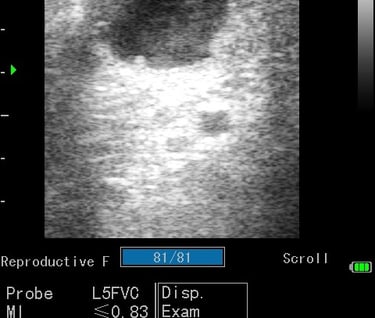

Gynécologie